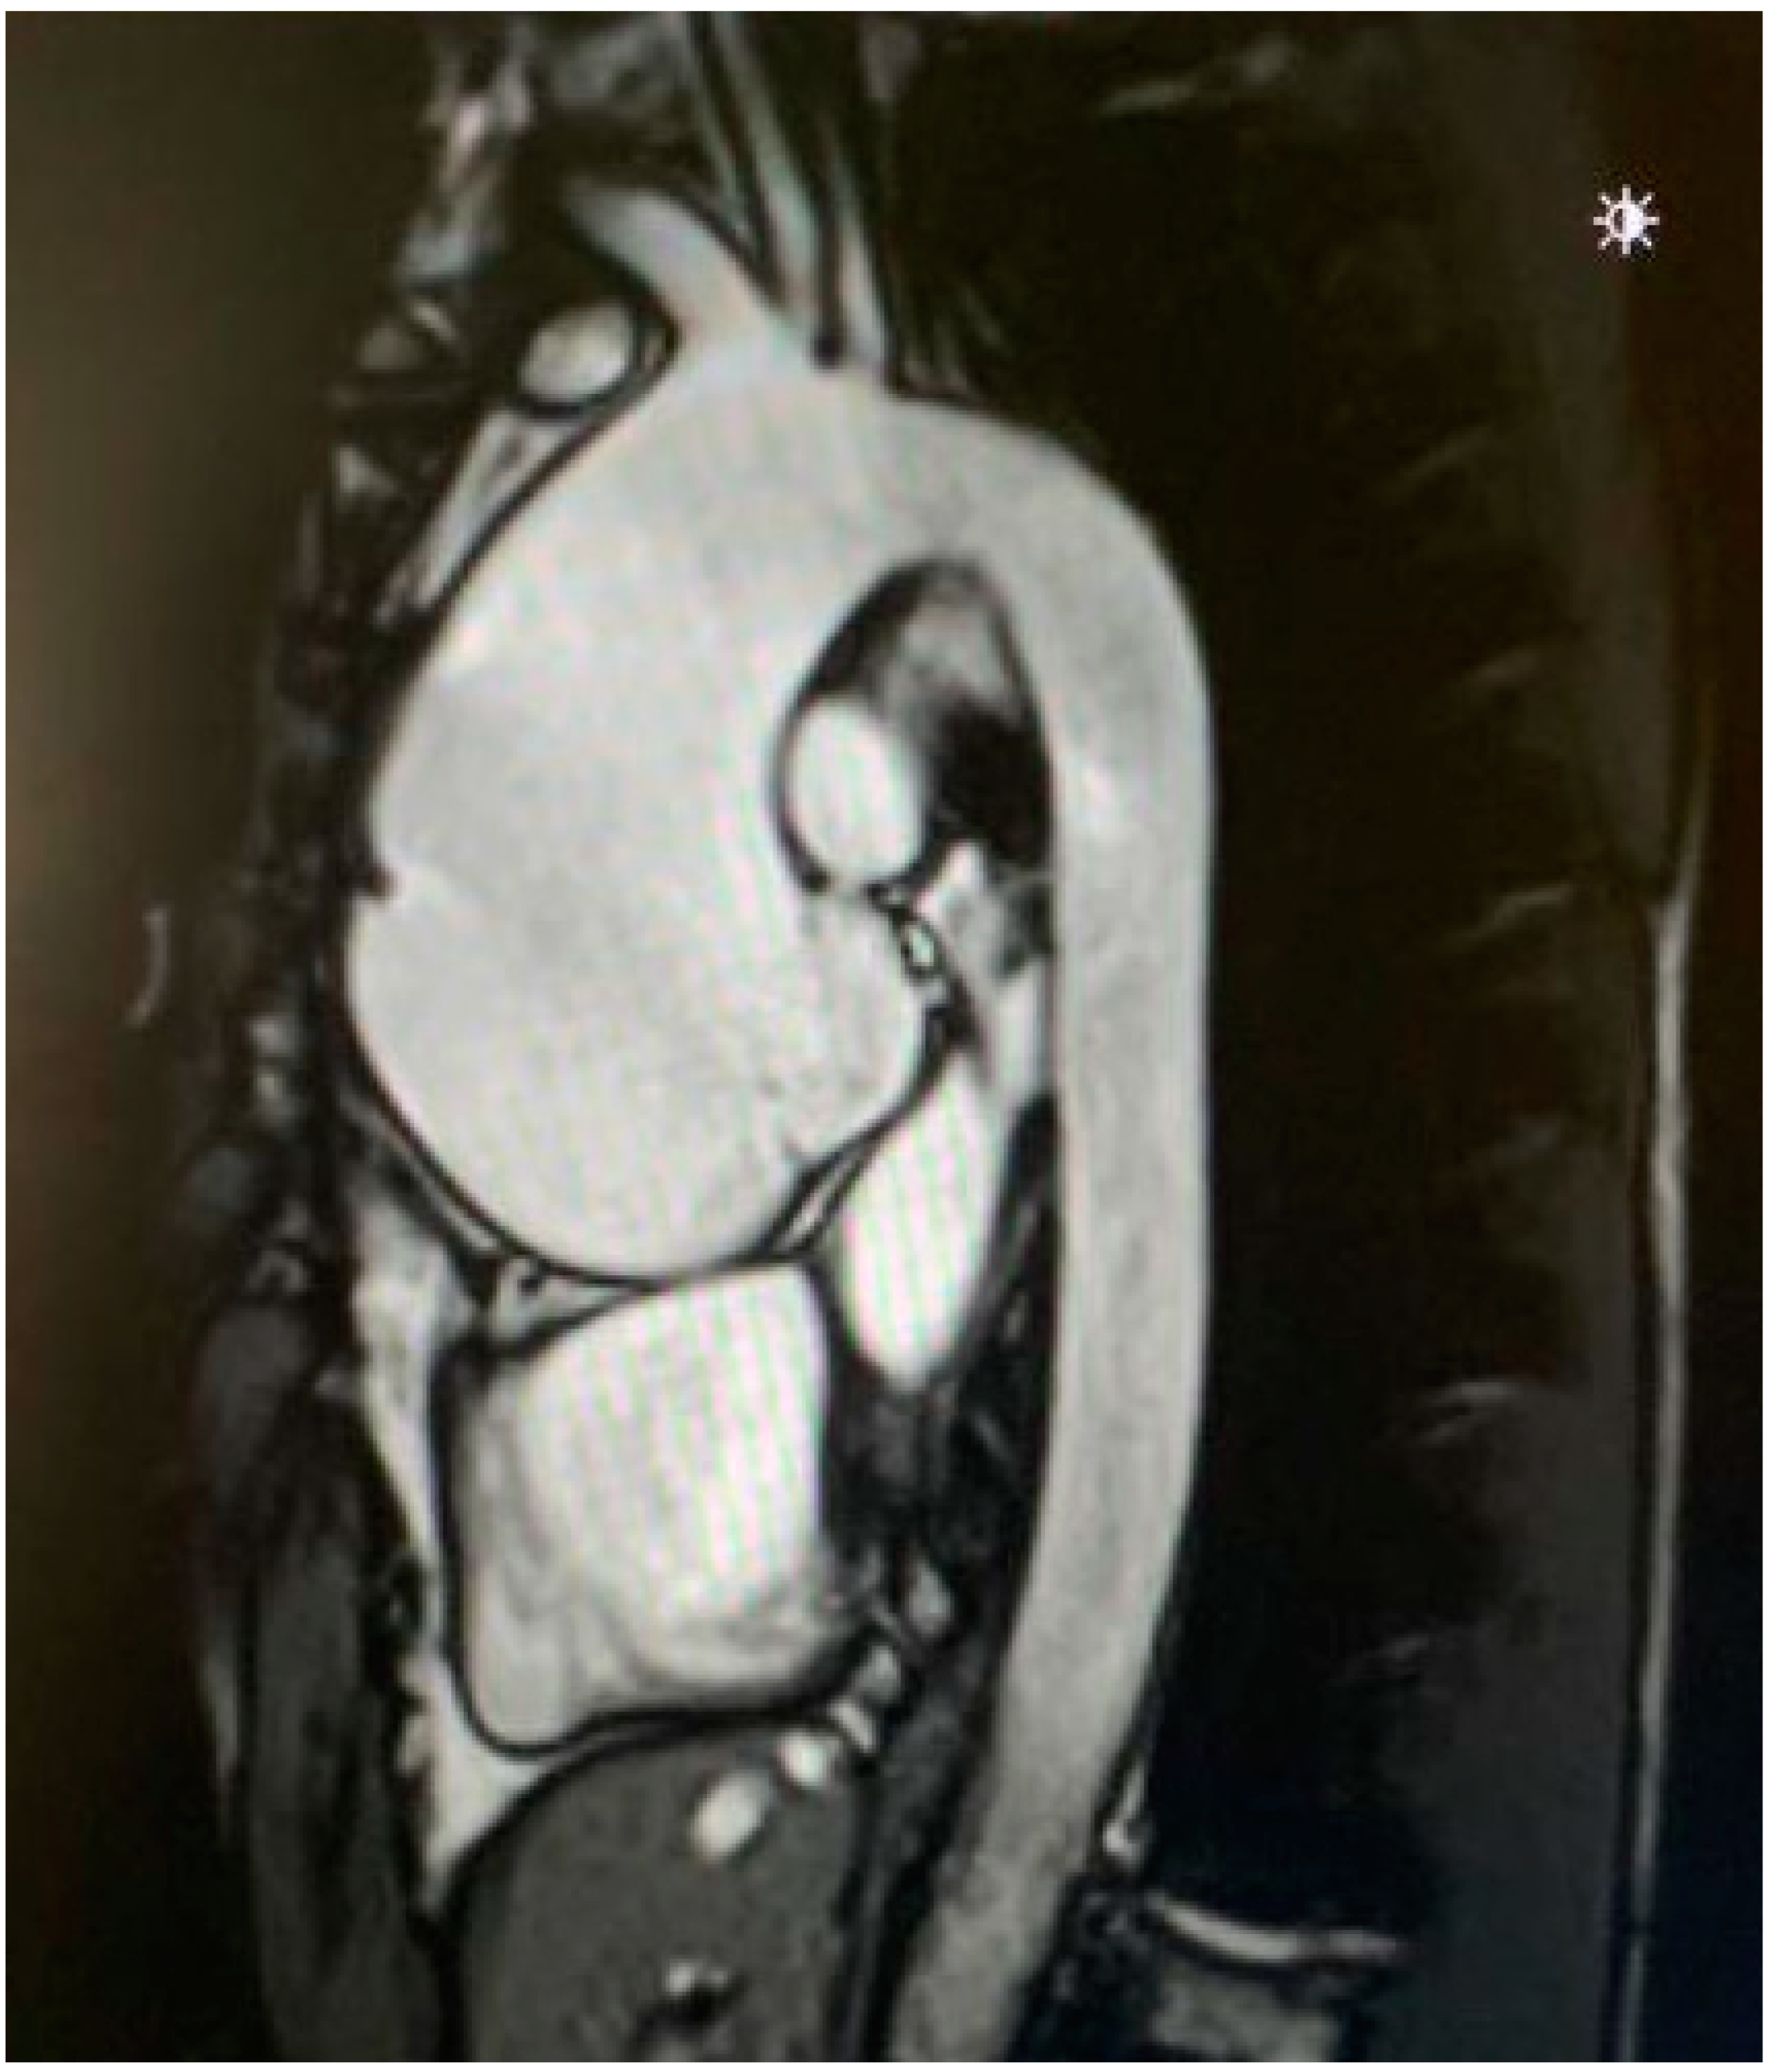

2. Measuring the Aortic Root and Ascending Aorta